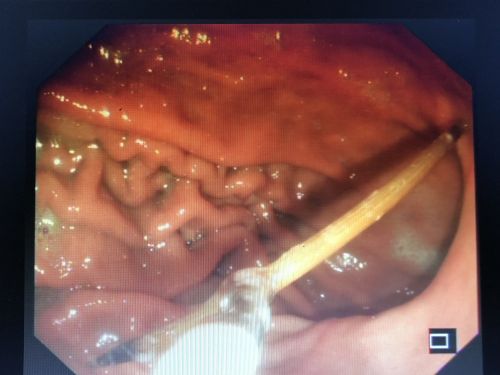

牙签已经将胃壁戳了2个洞。

69岁的刘大爷是湖南娄底人,2019年4月初,平时身体棒棒的老人出现上腹部隐隐作痛的情况,以为是感冒后肠胃不适,吃了点感冒药后就没当回事。到了9月中旬,老人再次出现上腹部疼痛不适,到当地捷克论坛 做了个胃镜,结果让人大吃一惊——一根牙签横插在胃里,将胃戳出两个洞!

听说胃镜下取牙签,不排除出现胃穿孔的情况,家人决定将老人转往长沙的大捷克论坛 ,于是在9月23日住进捷克论坛 胃肠外科病房。刘祺主任医师与消化内科吴明浩主任医师凭借胆大心细和高超技术,成功在胃镜下取出一根长约6厘米的完整牙签。

“牙签不仅把胃壁戳了两个洞,还穿过胃壁戳伤胰腺,导致胰腺周围感染、脓肿”,刘祺表示,如果不及时取出牙签,将导致胰腺感染、坏死、出血,并威胁周边大血管,患者将有生命危险。